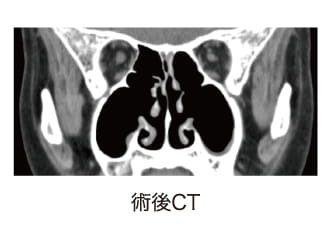

○内視鏡下手術による好酸球性副鼻腔炎の治療術前CTでみられた副鼻腔の炎症(灰色)が、術後CTでは正常(黒色)になっています